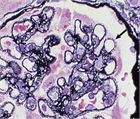

1. 糸球体毛細血管係蹄の上皮側に免疫複合体が沈着して発症し進展する糸球体障害で、非選択性の大量タンパク尿を呈する。確定診断は腎生検による。